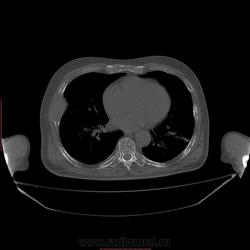

Пациент 1946 г.р., состоит на Д учете в онкодиспансере по поводу с-ч кожи (базалиома), прошел курс лучевой терапии, в 2009г на Ргенографии выявили образование 7 ребра, направили на Кт, на КТ (2009г) был выставлен д-з ГКО, пункционная биопсия не произведена. А сейчас вот такая картина, с множественными литическими очагами в костях грудного склета + образование 7 ребра, с отрицательной динамикой.

повторно взяли пациента, сняли кости таза, такая же картина- множественные очаги литической деструкции. Заключение: больше данных за миеломную болезнь.